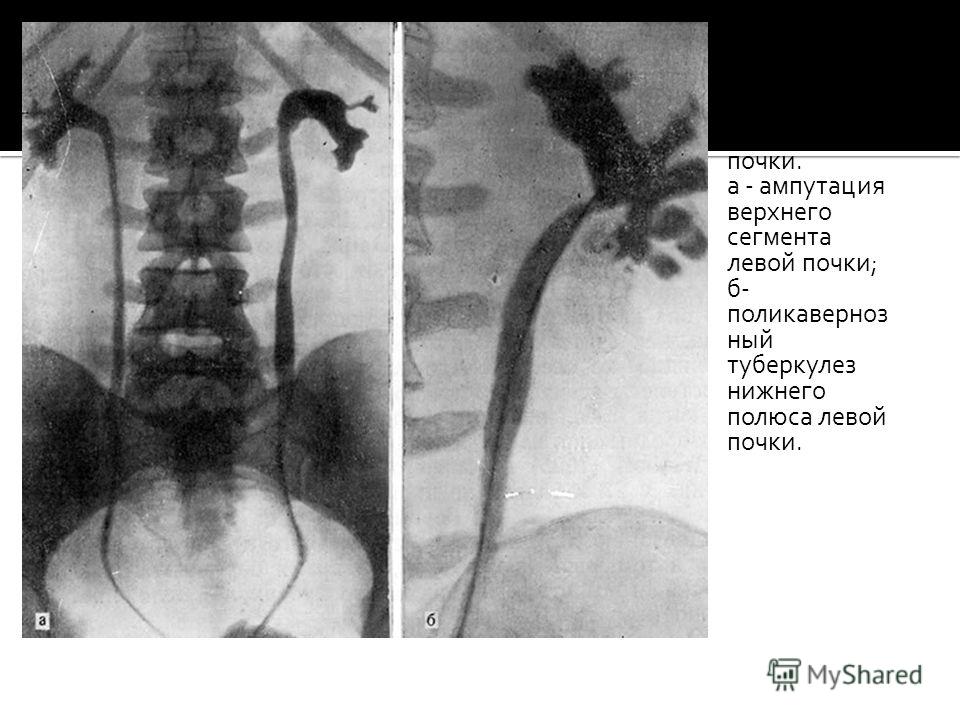

Понимание кавернозного туберкулеза почки